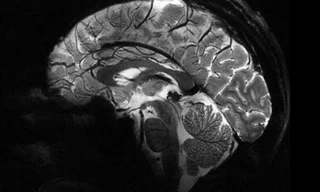

Bộ não với khả năng chế ngự nỗi sợ khi đu mình trên những vách đá dựng đứng của vận động viên leo núi Alex Honnold là đề tài thu hút các nhà nghiên cứu.

60 năm sau cái chết của thiên tài vật lý Albert Einstein, các lát não còn lại của nhà khoa học vĩ đại nhất thế kỷ XX vẫn đang được trưng bày công khai tại một địa điểm duy nhất trên thế giới.

Trong quá trình khám nghiệm tử thi Albert Einstein, bác sĩ Thomas Harvey là người phát hiện nguyên nhân cái chết do vỡ động mạch chủ. Sau này, ông cũng là người giữ bộ não trong nhiều năm.